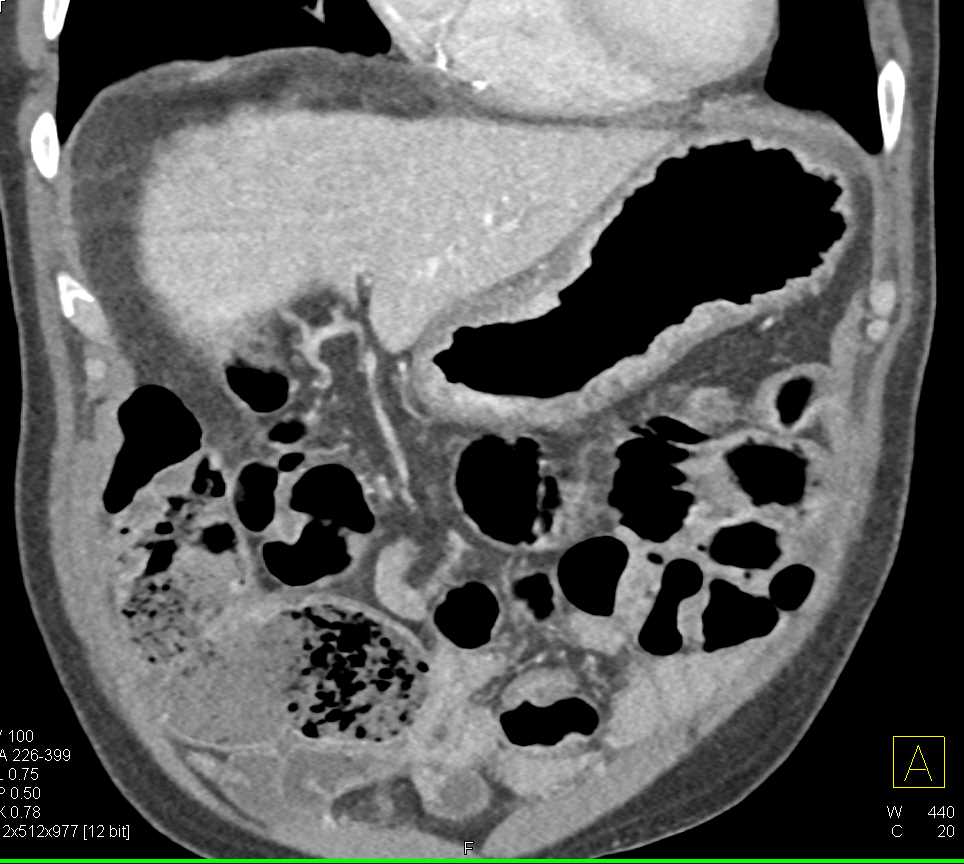

Gastric Adenocarcinoma Which is Infiltrating